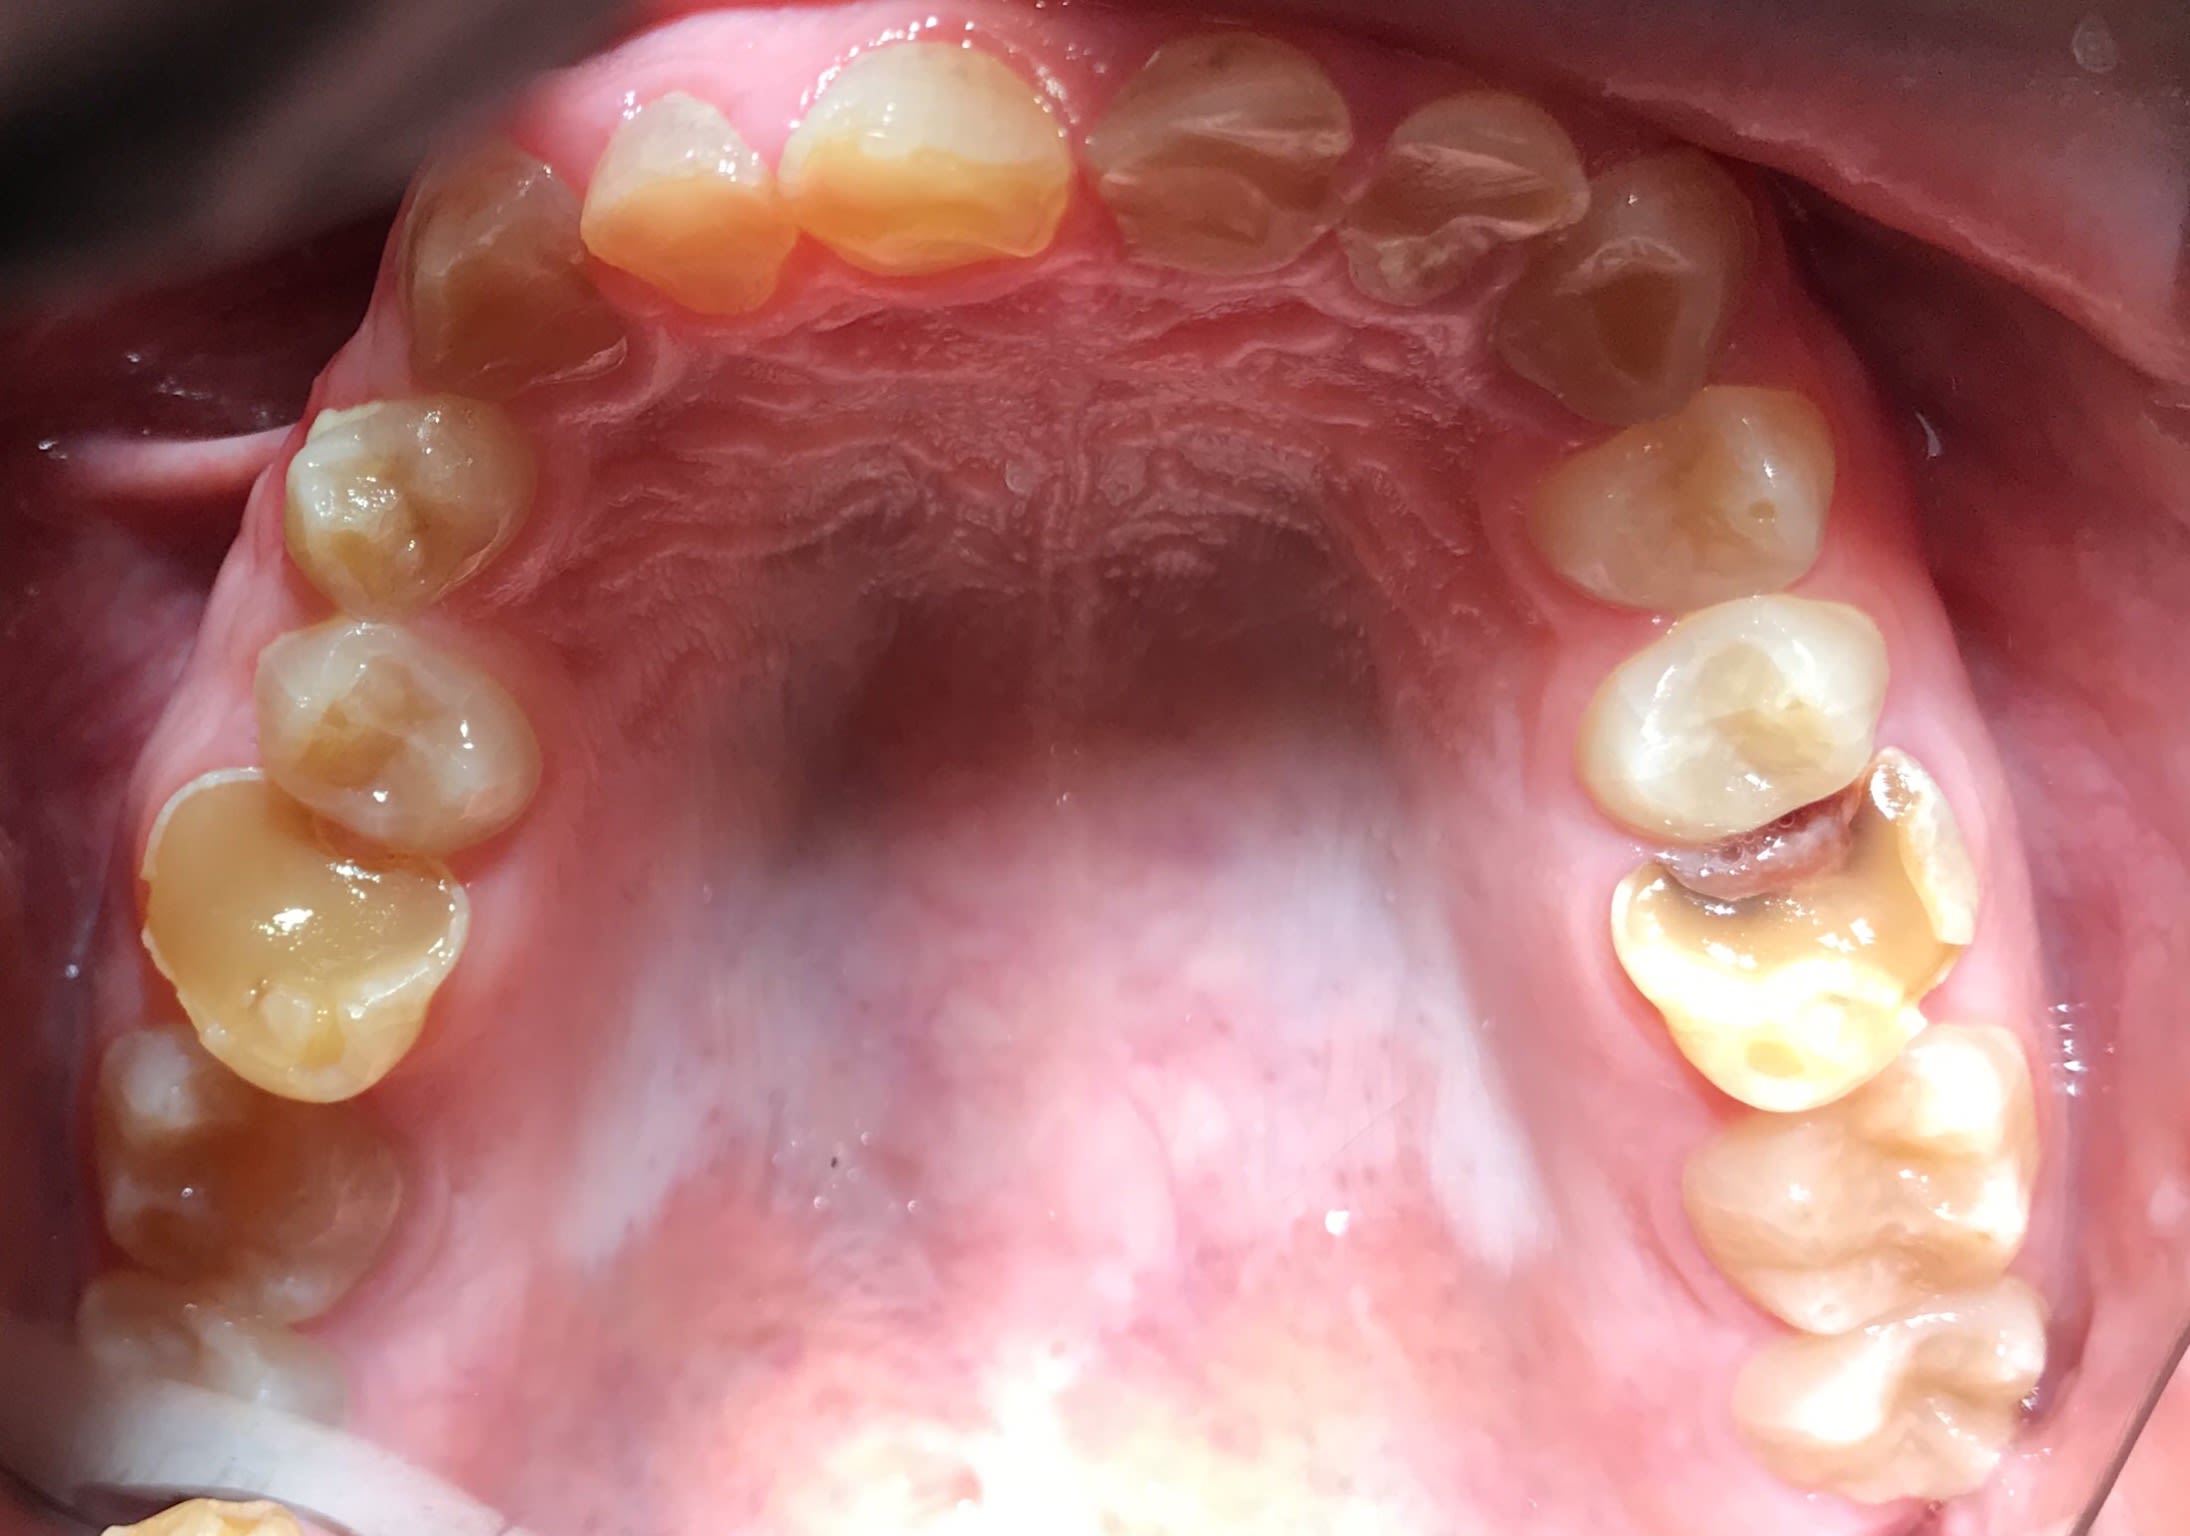

Bonjour je suis lenovo ici . Quelqu’un pourrait-il me donner toutes les étapes pour faire ce cas ? Que faut-il faire précisément ? Le patient n’a pas de contraintes financières. Pas de lésions apicales. Uniquement des usures de dents.

la photo peut tromper mais il semble être en clII,2 en plus.

Les photos ne sont pas dingues, mais les usures semblent très majoritairement antérieures. Pourquoi?

Et le fait que 17 18 27 28 semblent intactes alors qu'apparemment il y a des antagonistes intactes aussi

Je suspecte un cas d'ortho non traité sous jacent XXL ... que j'aimerais voir sa télé de profil ...